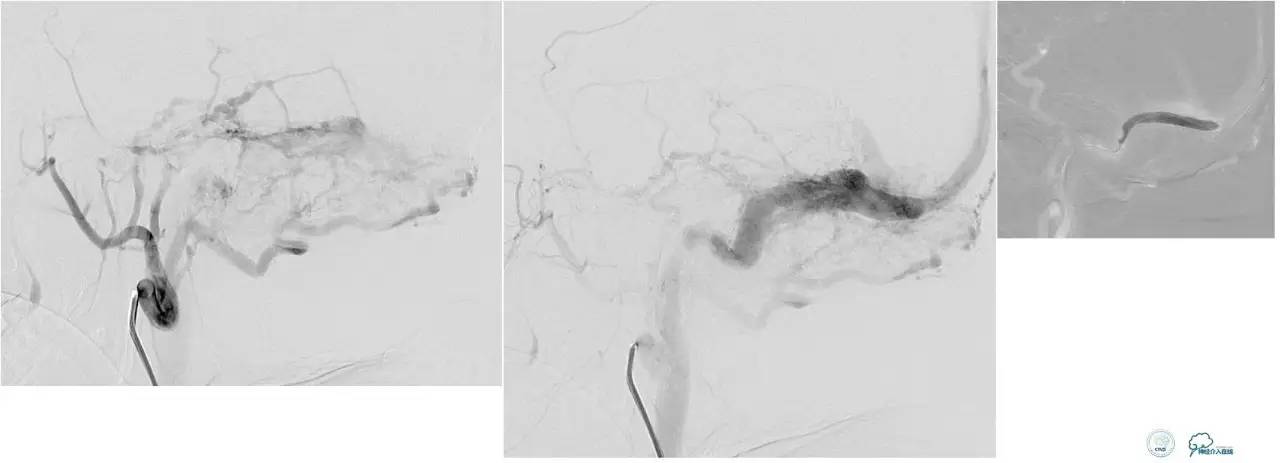

侧窦区DAVF,直接引流入横窦,为保护窦,横窦放入球囊8*80。

最终栓塞结果,窦通畅。

文献中图片,上矢状窦内放置球囊保护。

参考:Balloon-assisted transarterial embolization of intracranial dural arteriovenousfistulas. J Neurosurg 2009;110:921–928.

文献中图片,经颈外动脉栓塞,在椎动脉内放置保护球囊,防止通过脑膜后动脉逆向栓塞椎动脉。

参考:Endovascular treatment of high-risk tentorialdural arteriovenousfistulas: clinical outcomes. Neuoradiology2009;51:103-111.